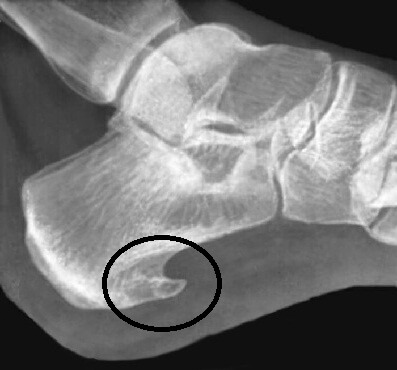

- Фасциит (иначе – пяточная шпора). Внутрикожное образование с периодами обострения и выраженными болями с пульсацией при ходьбе.

- рентгенологическое обследование;

- МРТ или КТ-исследование, УЗИ;